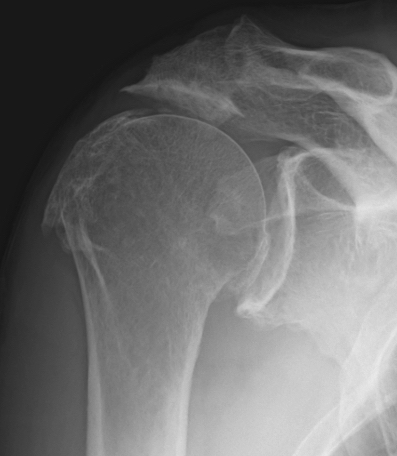

Xray

Acetabularization of the acromion and osteoarthritis